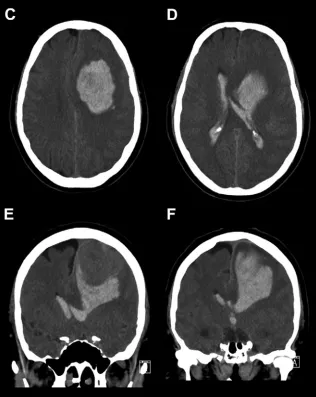

增强CT扫描揭示出险情:其左侧额上回区域发现一个与硬脑膜相连的类圆形病灶,内部已见出血迹象(图1A,B)。诊断指向一种罕见的脑膜瘤相关出血。

就在入住地区医院约6小时后,患者被紧急转往上级神经外科中心。转运途中,惊险一幕发生——患者突然陷入昏迷!经紧急抢救,生命体征方趋稳定。抵达后紧急复查CT,结果令人震惊:原病灶周围爆发大量脑实质内及脑室内出血(图1C–F),颅内情况急剧恶化。综合研判,这是一例极其罕见的、与良性脑膜瘤相关的“两阶段”复发性大出血事件,第二波出血来势汹汹,直接危及生命。